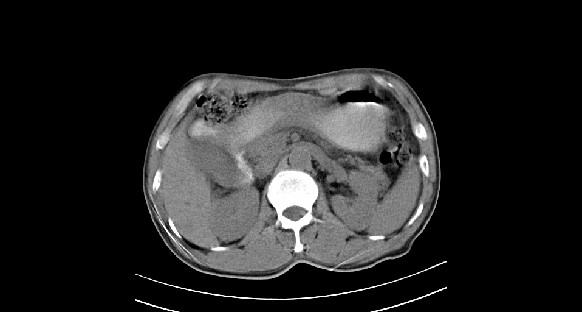

男性,70岁,体检b超发现左肾占位,请各位战友发表一下观点

左肾有两个病灶,且较大的病灶内可见点状钙化灶,增强扫描边缘也是呈渐进性强化,中央部分未见明显强化